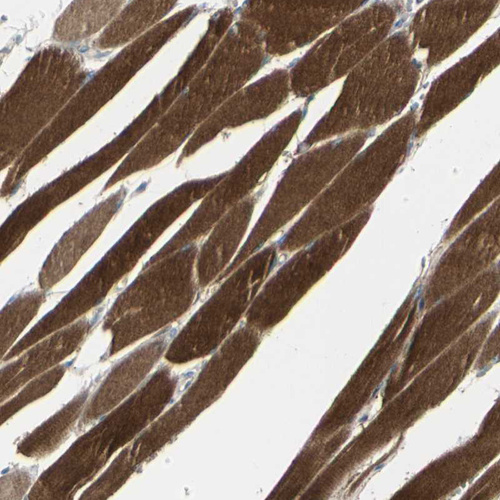

Immunohistochemistry analysis in human skeletal muscle and pancreas tissues using HPA008621 antibody. Corresponding CACNA2D1 RNA-seq data are presented for the same tissues.